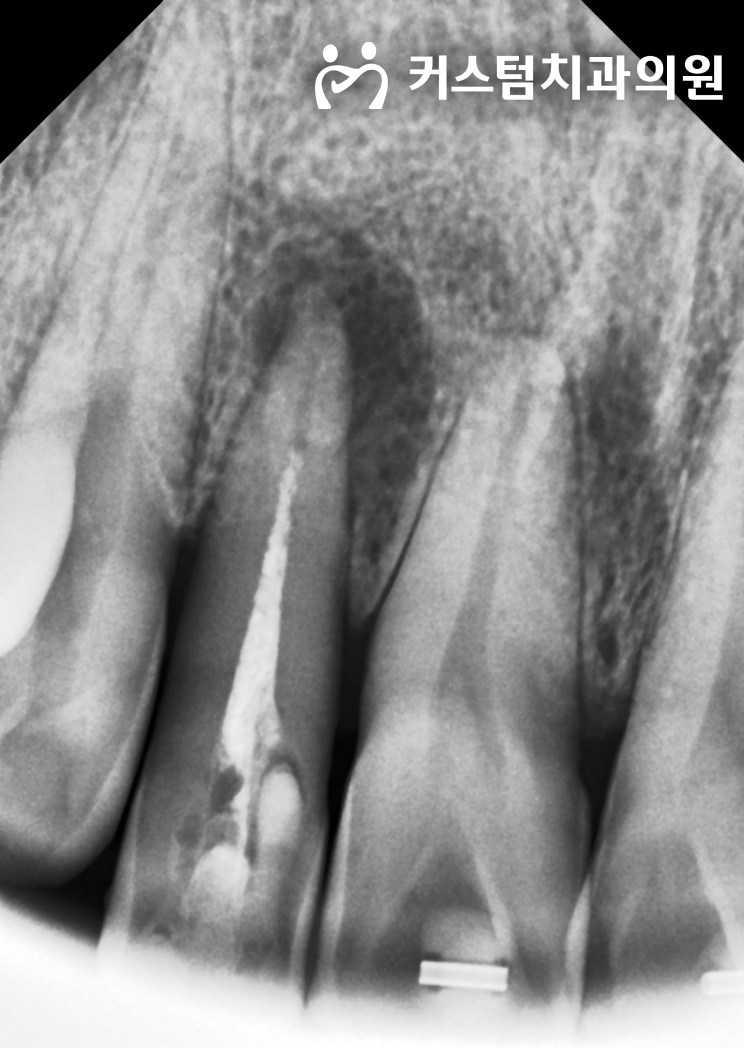

2023년 7월 21일 첫 진료 시 촬영한 방사선 사진입니다.

더 심각한 문제는 방사선 사진에서 확인됩니다.

우측 측절치 뿌리 끝에 잇몸뼈를 광범위하게 녹여버린 치근단 염증 병소가 관찰됩니다.

즉, 치열이 틀어진 진짜 원인은 치아가 삐뚤게 자란 것이 아니라, 뿌리 끝에서 팽창한 염증성 조직이 물리적인 압력을 가해 치아를 바깥쪽으로 밀어냈기 때문이었습니다.